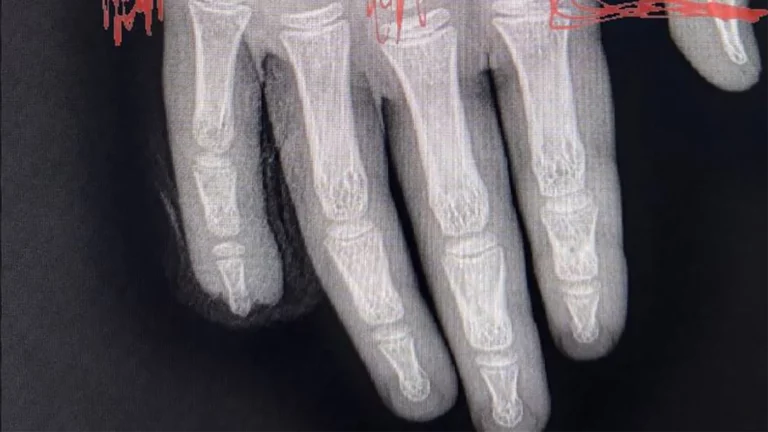

«112» со ссылкой на мать пострадавшей писал, что детей отвели на физкультуру, для чего они спустились на первый этаж и встали между спортзалом и дверью. В это время из спортзала выходила другая группа, и воспитательница попросила ее дочь и других детей прижаться к стене, чтобы дать пройти остальным. Девочка прижалась и положила руку на открытую дверь. В этот момент один из мальчиков закрыл дверь и придавил ей палец.

Мать сообщила, что ребенок начал истекать кровью, однако сотрудники детского сада якобы просто меняли ей повязку на пальце и ждали приезда родителей.

Также женщина рассказала «112», что ее дочке грозит ампутация пальца из-за торчащей кости.